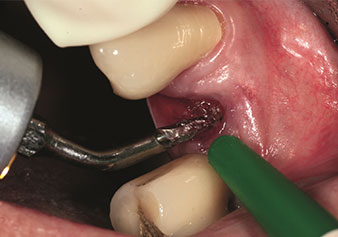

Periotomo sottile (strumento EX1)

Fig. 1: Periotomo sottile (strumento EX1).

Foto: © Dott. Torsten Conrad (Bingen a. Rhein)

Un’applicazione che viene spesso sottovalutata è l’estrazione atraumatica di radici di denti o frammenti di radici nell’ambito della gestione alveolare. I periotomi sottili, che sono attualmente disponibili in due versioni (EX1 ed EX2 di W&H), possono essere, inoltre, utilizzati per rimuovere con facilità denti che hanno precedentemente subito uno specifico trattamento endodontico o con radici anchilosate. Ne consegue l’estrazione di alveoli in cui i tessuti duro e molle sono entrambi completamente intatti in quanto è generalmente possibile evitare la riflessione.

Ciò pone le basi ottimali per un trattamento con impianto immediato o successivo (Figure 1 e 2 inserite grazie alla gentile concessione del Dott. Torsten Conrad, Bingen a. Rhein).